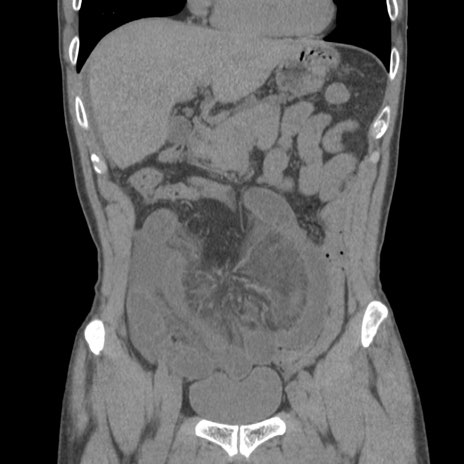

症例56 CT(冠状断像)

脂肪ウインドウ